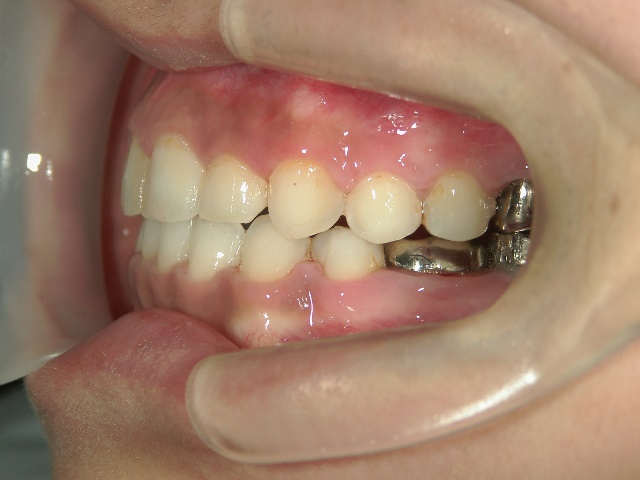

矯正歯科 治療後矯正歯科 全顎ワイヤー矯正 治療後矯正歯科(全顎ワイヤー矯正)治療後

矯正歯科 治療後

no.28_6958_治療後_右.jpgno.28_6958_治療後_正面.jpgno.28_6958_治療後_左.jpg